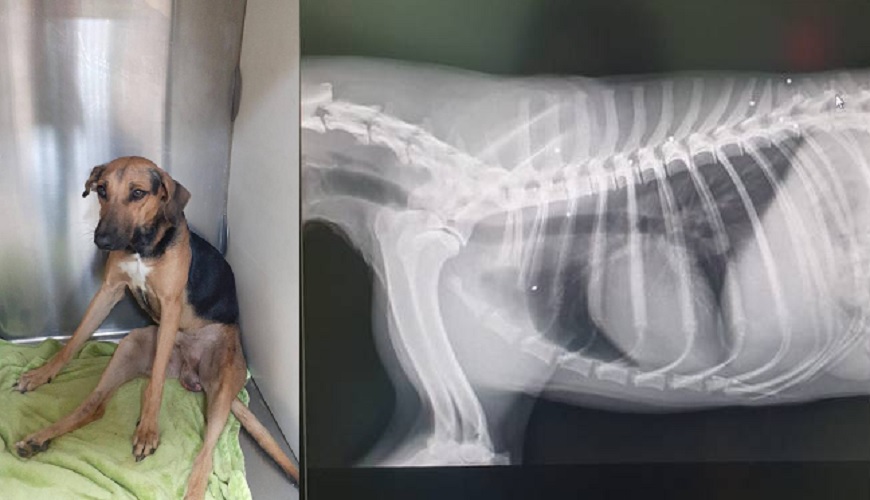

Fourhour operation in Abu Dhabi helps dog survive from 11 gunshots Can Dogs Be Around Gunshots don’t take your dog hunting until he’s properly trained around gunshots. This is important because the. how to introduce a puppy to gunfire. That’d be like having a canoe without a. Let’s go over some of the best methods to introduce and condition your dog to gunfire! Positive reinforcement is considered the pinnacle. Depending on the dog, the.. Can Dogs Be Around Gunshots.